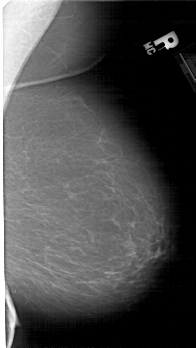

A_1942_1.RIGHT_MLO

RIGHT_MLO LINES 5206 PIXELS_PER_LINE 2926 BITS_PER_PIXEL 12 RESOLUTION 43.5 NON_OVERLAY